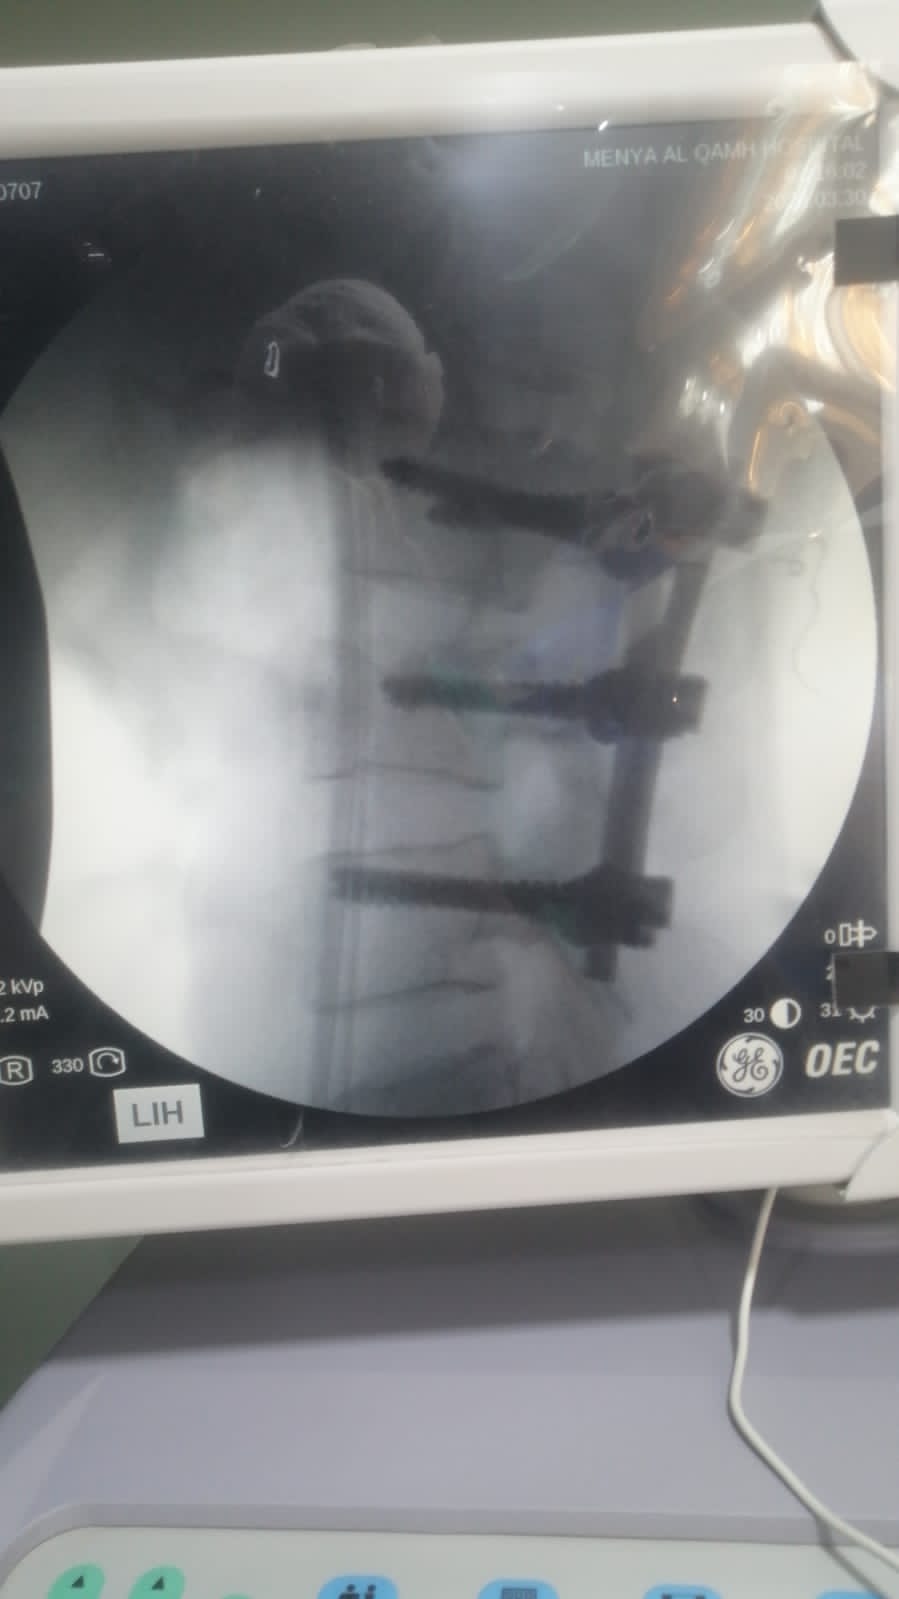

وأشار محمود عبدالفتاح مدير الإعلام والعلاقات العامة بالمديرية إلى أن مستشفى منيا القمح المركزي استقبلت الشاب بحالة صحية سيئة حيث تم توقيع الكشف الطبي عليه فور وصوله، وإجراء كافة الفحوصات الطبية والأشعات اللازمة، والتي أظهرت وجود كسر بالفقرة القطنية الثالثة مصحوب بضغط على الحبل الشوكي وجذور الأعصاب، وعلى الفور تم إجراء العملية الجراحية المتقدمة للمرة الأولى لتثبيت الفقرات باستخدام القضبان والمسامير، مع توسيع القناة العصبية ورفع الضغط عن الحبل الشوكي وجذور الأعصاب، للحفاظ على الوظائف الحركية والعصبية، لافتاً أن المريض حالته مستقرة بفضل الله، مع تحسن ملحوظ في القدرة على الحركة، ويخضع حالياً للمتابعة الطبية تحت إشراف أطباء المستشفى.